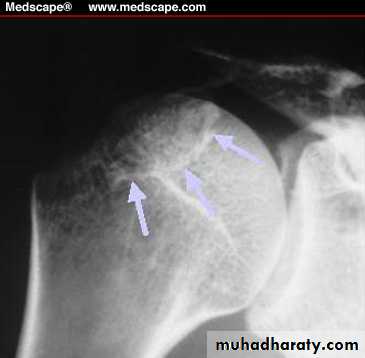

Fracture proximal humerus

This type of fracture occur in old and middle age osteoporotic people .

In the majority of the cases displacement is not marked , only 20% of cases has considerable displacement .

The fracture occur due to fall on out stretched arm

Classification of this fracture called neer classification .

Clinically : history of trauma , pain ,loss of function , swelling , bruises on the skin , sign of axillary nerve or brachial plexus injury may be detected .X-ray :a-p , lat.view or axillary view should be taken to exclude associated dislocation .

Proximal humerus fracture